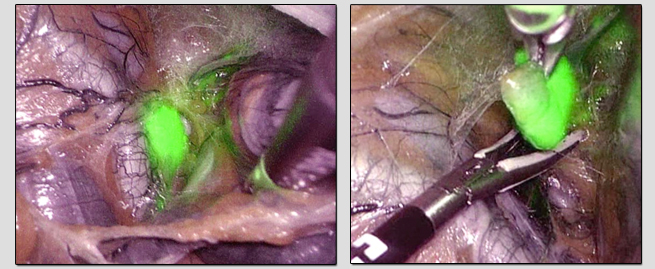

“Surgical Technique: indocyanine green and infrared fluorescence in sentinel lymph node mapping in endometrial cancer” é o nome do trabalho que foi contemplado com o prémio de melhor vídeo de técnica cirúrgica.

Num vídeo de cerca de quatro minutos, “ilustrámos as tipificações atuais, a forma como utilizamos o verde de indocianina no cancro do endométrio e a própria cirurgia no que toca à pesquisa do gânglio sentinela com esta técnica minimamente invasiva”, refere Nuno Nogueira Martins, coordenador da Unidade de Oncologia Ginecológica do Serviço de Ginecologia e Obstetrícia do Centro Hospitalar Tondela-Viseu.

Imagens da cirurgia (fotos de Nuno Nogueira Martins)

Sara Sousa Sales, Ângela Melo, Sónia Gonçalves, Francisco Nogueira Martins e Nuno Nogueira Martins são os autores deste vídeo, que se refere a uma “técnica pioneira e promissora realizada através de cirurgia minimamente invasiva para a pesquisa de gânglio sentinela, permitindo o diagnóstico de metástases ganglionares em situações de cancro do endométrio”.